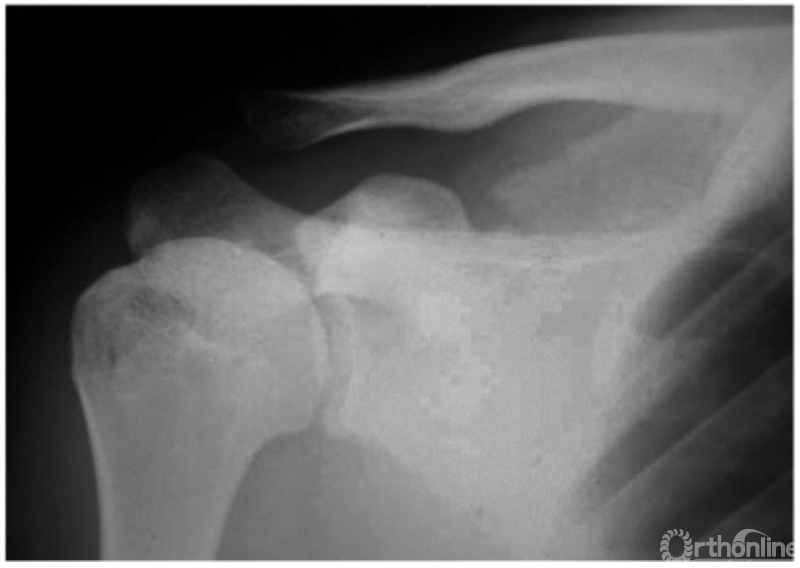

2. 肩锁关节脱位并喙锁韧带断裂

本例由于肩锁韧带及喙锁韧带均断裂致喙锁间隙扩大与肩锁关节脱位(图4)。